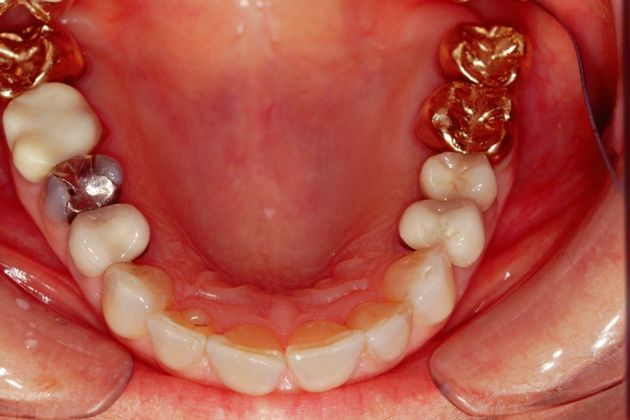

Procedures; TMJ CAT scan, TMJ deprogramming, whitening, sedation dentistry, reconstruction of all the back and upper front teeth with porcelain crowns, bite guard therapy. This foster care provider wanted to be free of the pain in her jaw joints. She had a lifelong history of grinding, many of her back teeth were breaking down and her bite was off. Her treatment was performed in sections to spread out the cost. She and her husband were so pleased with the result!